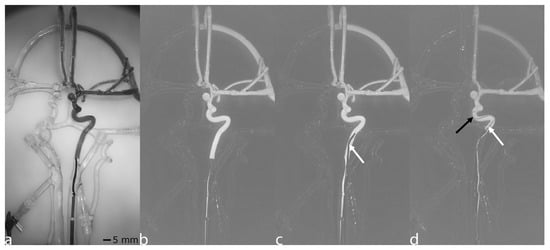

AngioSim’s RM mode mimics the roadmap generation process of a real angiography unit, enhancing vascular visualization. When ‘Cine’ is pressed, a subtraction mask is generated by accumulating all recorded frames until ‘Cine’ is released. The accumulation is achieved by taking the minimum intensity of each pixel across frames to enhance vessel visibility under contrast agent injection, providing a clear image of the contrasted vessels. The mask generation is displayed in real time to guide the procedure, as illustrated in Figure 3a, which shows an accumulated RM mask. When a mask is successfully captured, pressing ‘X-ray’ subtracts the mask from the live image to reveal the contrasted vascular structures, as shown in Figure 3b. Figure 3c,d show how the RM mode highlights changes in the image, such as the movement of catheters and wires. Additional image processing, including brightness adjustments, is applied to further refine the RM image.

Figure 3. Roadmap (RM) simulation. (a) Accumulated RM mask showing the contrasted vessel outline generated from multiple frames. (b) The resulting RM obtained by subtracting the RM mask from the live feed. (c) RM with a guiding catheter visible within the vessel, indicated by a white arrow. (d) RM generated using a different mask, with the microcatheter shown by a white arrow and the microwire by a black arrow.

While AngioSim adequately displays catheters and guidewires sufficiently, 24% of participants still considered the simulation unrealistic, underscoring the need for further improvements. Future enhancements should focus on controlling the camera via a joystick, enabling camera rotation around the silicone model and incorporating a second camera for biplanar imaging. However, these upgrades may not fully resolve the issue of overlapping vascular structures, as the system relies on light-based imaging instead of the penetrating capabilities of radiation. Additionally, the grayscale display makes it challenging to distinguish between microcatheters and microwires without markers for ionizing radiation as depicted in Figure 2b and Figure 3d and to identify the exact position and orientation of other medical devices such as stent retrievers.